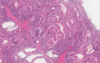

Dx?

Hamartomatous polyps

(Peutz-Jeghers syndrome)

Dx?

Hamartomatous polyps

(Peutz-Jeghers syndrome)

Shows arborizing smooth muscle of the jejunum

Dx?

Hamartomatous polyps

(Peutz-Jeghers syndrome)

Shows arborizing smooth muscle + lobulated glands without dysplasia